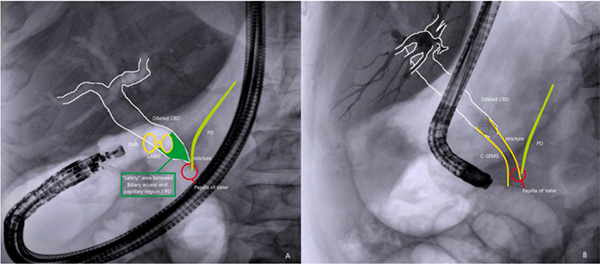

(A)EUS-CDS通过LAMS支架在胆总管中段建立通路,远离乳头和胰管“危险区”;(B) 传统ERCP需经十二指肠乳头入路,易造成胰管损伤。本研究证实,(A) 路径可使术后胰腺炎风险降低75%。